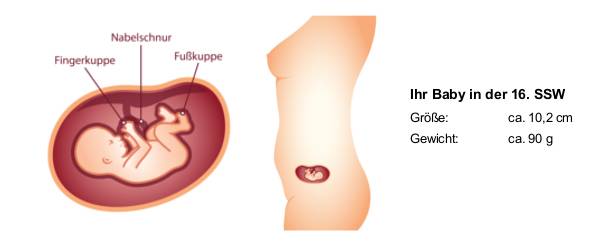

Расположение плода на 15-й неделе беременности: фотографии и иллюстрации